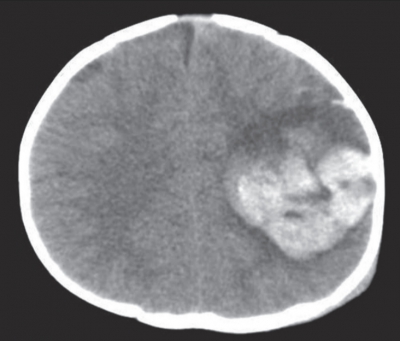

血液所見:赤血球320万、Hb 10.2g/dL、Ht 30%、白血球14,000、血小板25万、PT-INR 1.3(基準0.9~1.1)、APTT 98.3秒(基準対照37.1)、血漿フィブリノゲン150mg/dL(基準186~355)。血液生化学所見:総蛋白4.5g/dL、アルブミン2.8g/dL、AST 30U/L、ALT 26U/L、LD 774U/L(基準120~245)、尿素窒素12mg/dL、クレアチニン0.6mg/dL、血糖120mg/dL。頭部単純CTを別に示す。